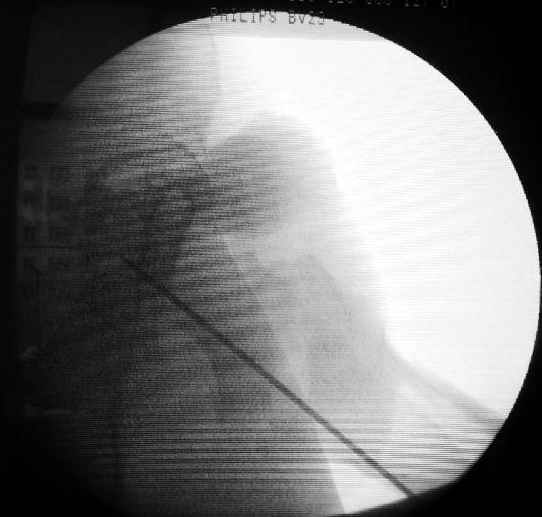

Как раз недавно у меня был примерный случай: больному 36 лет, поступил ночью, травма в результате мотоциклетной аварии, кроме чрезвертельного и спирального перелома левого бедра имеется переломы костей предплечья с этой же стороны. Скелетное вытяжение, а на следующий день больной про оперирован на ортопедическом столе с дистракцией. Чтобы не расколоть чрезвертельный перелом провели временную спицу ближе к переднему кортексу, из малого разреза костодержатель для репозиции, а фиксацию провели антиградным штифтом. Этапы операции на снимках.

Джолдас Кульджанов